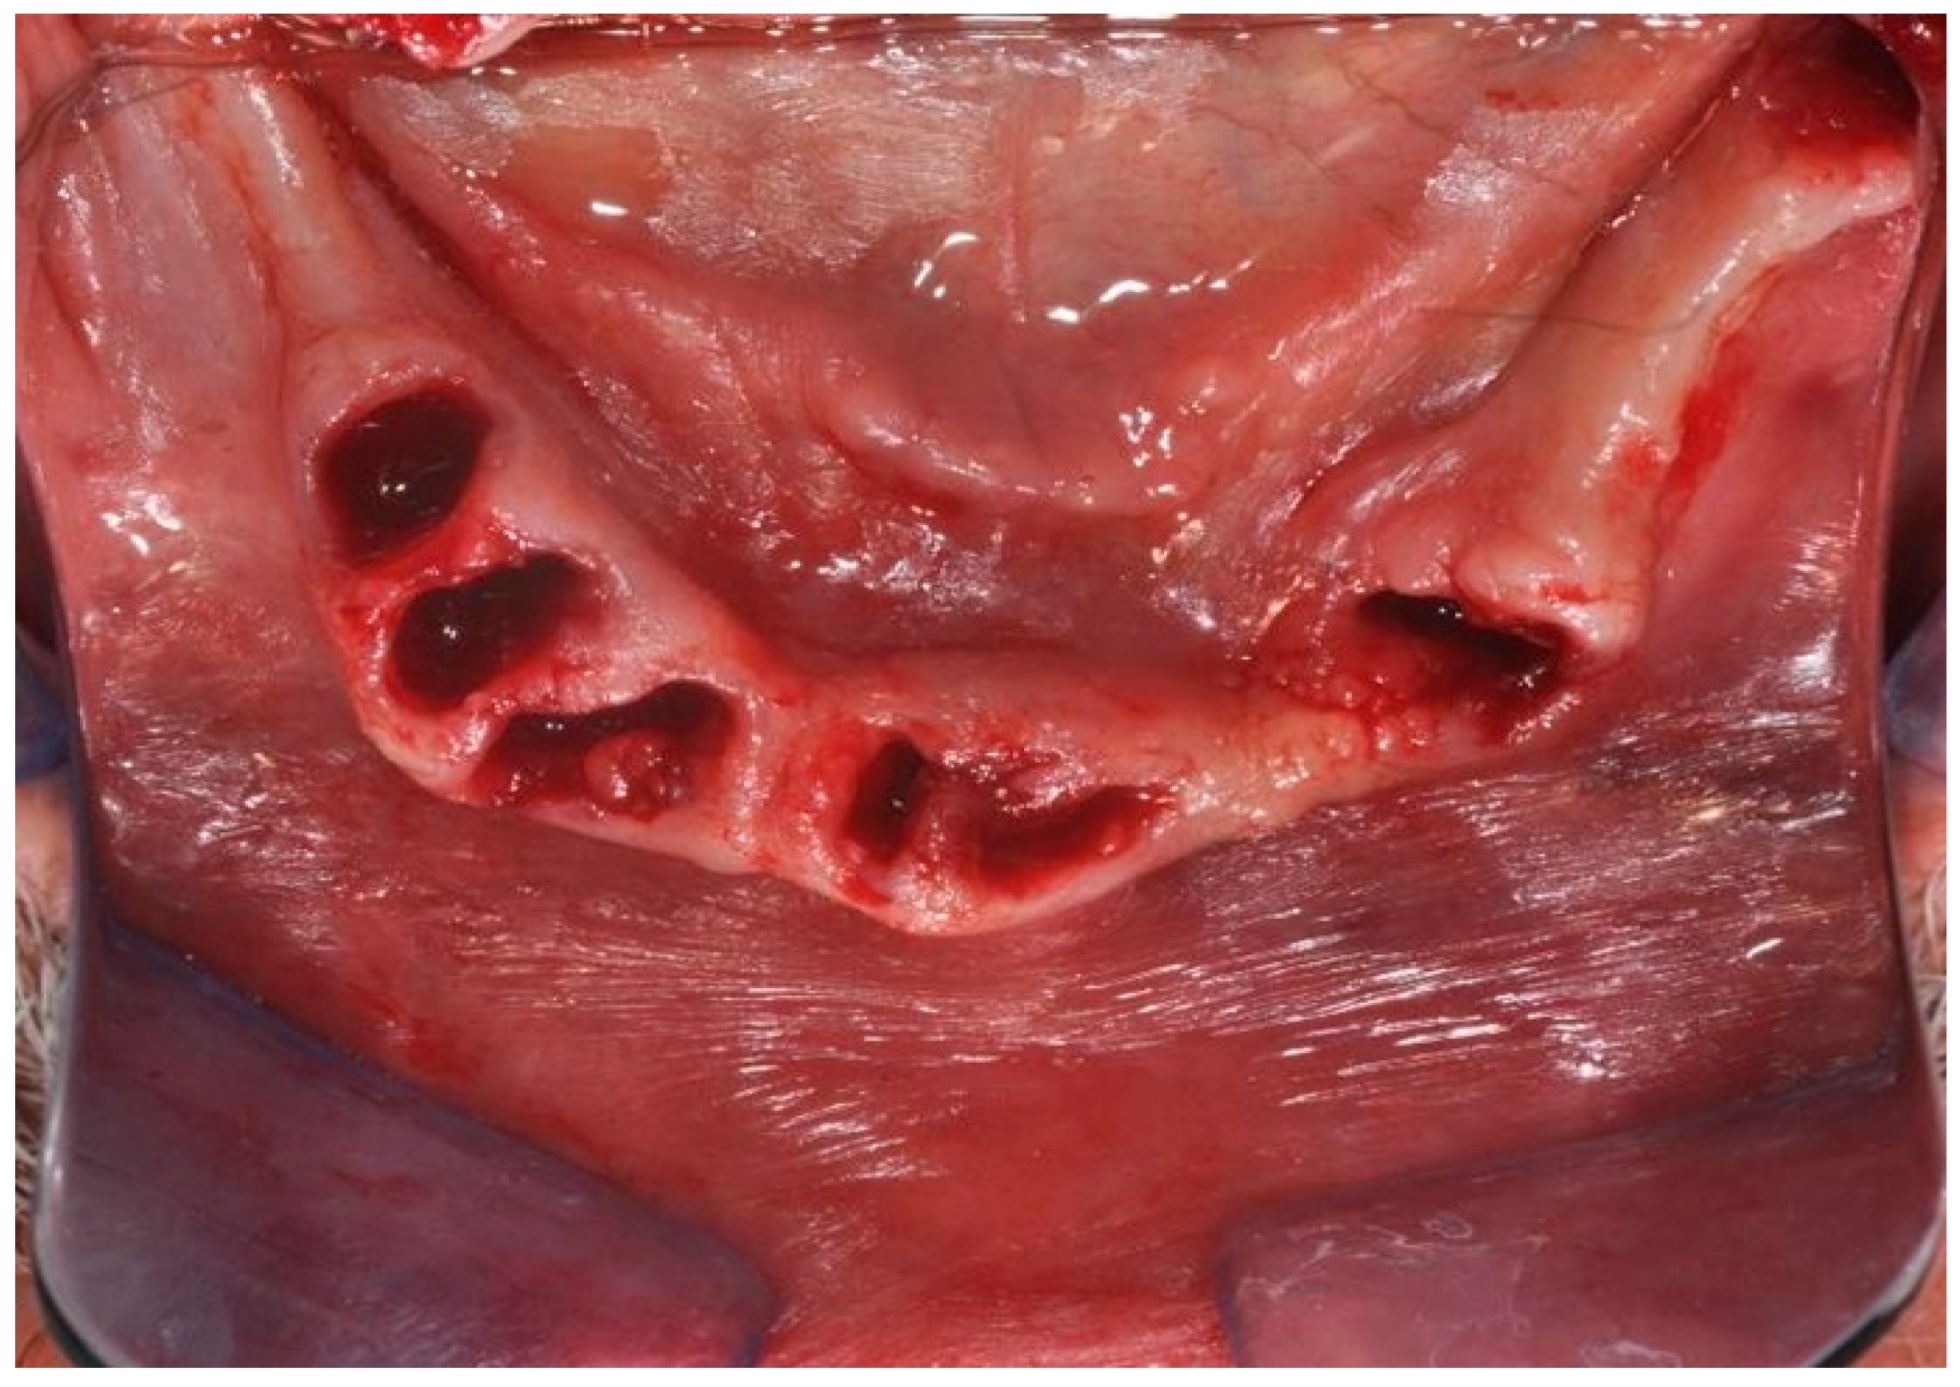

| Flanagan D. et al. [23] | J Oral Implantol | 2015 | clinical and radiographic: full-mouth radiographic series, panoramic and a bimaxillary cone beam computerized scan and mounted study casts | -One patient | Subject of 34 yo male; severely carious teeth and associated chronic abscesses (kidney transplant delayed) Comorbidities: IgA nephropathy, tabagism, hypertension and secondary hyperparathyroidism. Hemodialysis three times weekly. Ph. Therapy: Nephrocaps vitamin (B) supplement, amlodepine, besylate, cinacalcet, metoprolol, paroxetine. Bilateral compound ulnar and radial fractures, 2 blood transfusions. | Successfully treated with dental implant-supported fixed prostheses: fixed bimaxillary porcelain fused to metal implant-supported complete dentures |

| Hernández G. et al. [26] | Clin Oral Impl Res | 2019 | AI, MCI and TP reduction in mineral density of the cortical and trabecular bone in CRF patients and more severely in patients under haemodialysis compared to peritoneal dialysis | 1 IF in T | Mean follow-up of 116.8 months range from 84 to 192 months) | Renal transplant patients, are subjected pharmacological immunosuppression therapy |

| Flanagan D. et al. [23] | J Oral Implantol | 2015 | -Implant treatment for patients with IgA nephropathy (secondary hyperparathyroidism and osteodystrophy) may be successful. -Appropriate calcium therapy is important serum calcium to prevent inappropriate bone remodeling | 2 years | Long-term dialysis patient with end-stage renal disease (ESRD)also referred to as chronic kidney disease (CKD) due to IgA nephropathy complicated by severe secondary hyperparathyroidism and renal osteodystrophy | |